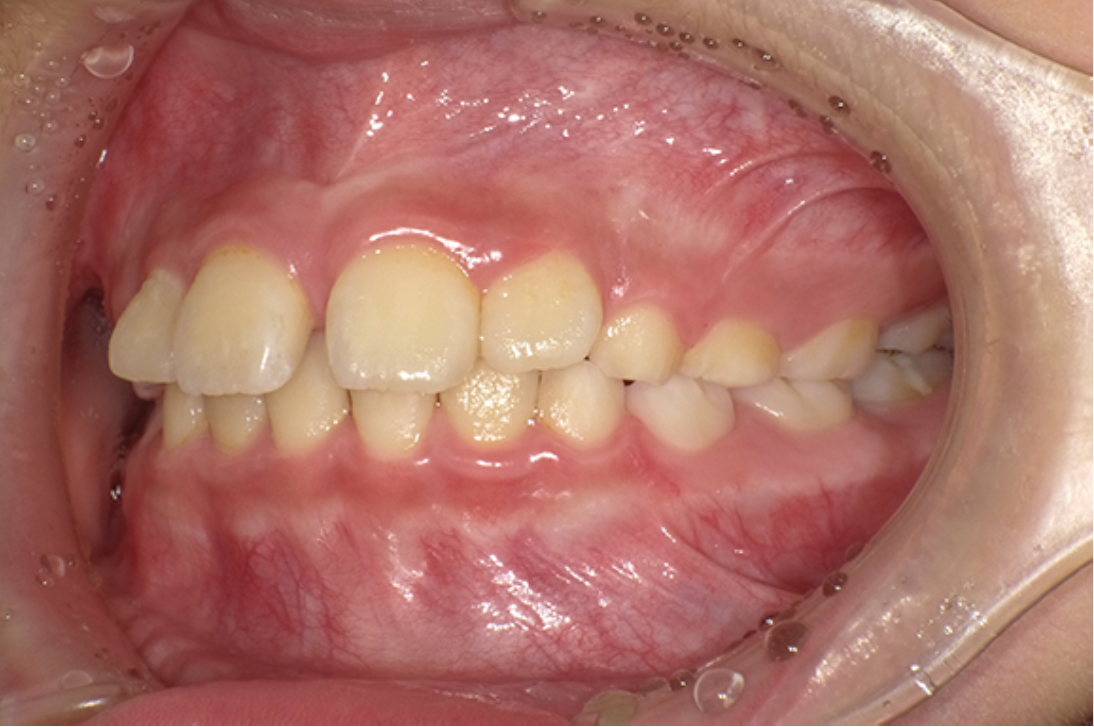

主訴:八重歯

診断:叢生

治療内容:唇側矯正治療

年齢:16歳

治療に用いた装置:マルチブラケット装置

抜歯or非抜歯:抜歯(上下顎両側小臼歯)

期間:14ヶ月

回数:14回

費用:957,000円(税込)

リスク・副作用:虫歯、歯肉炎、歯肉退縮、歯根吸収、後戻りなど